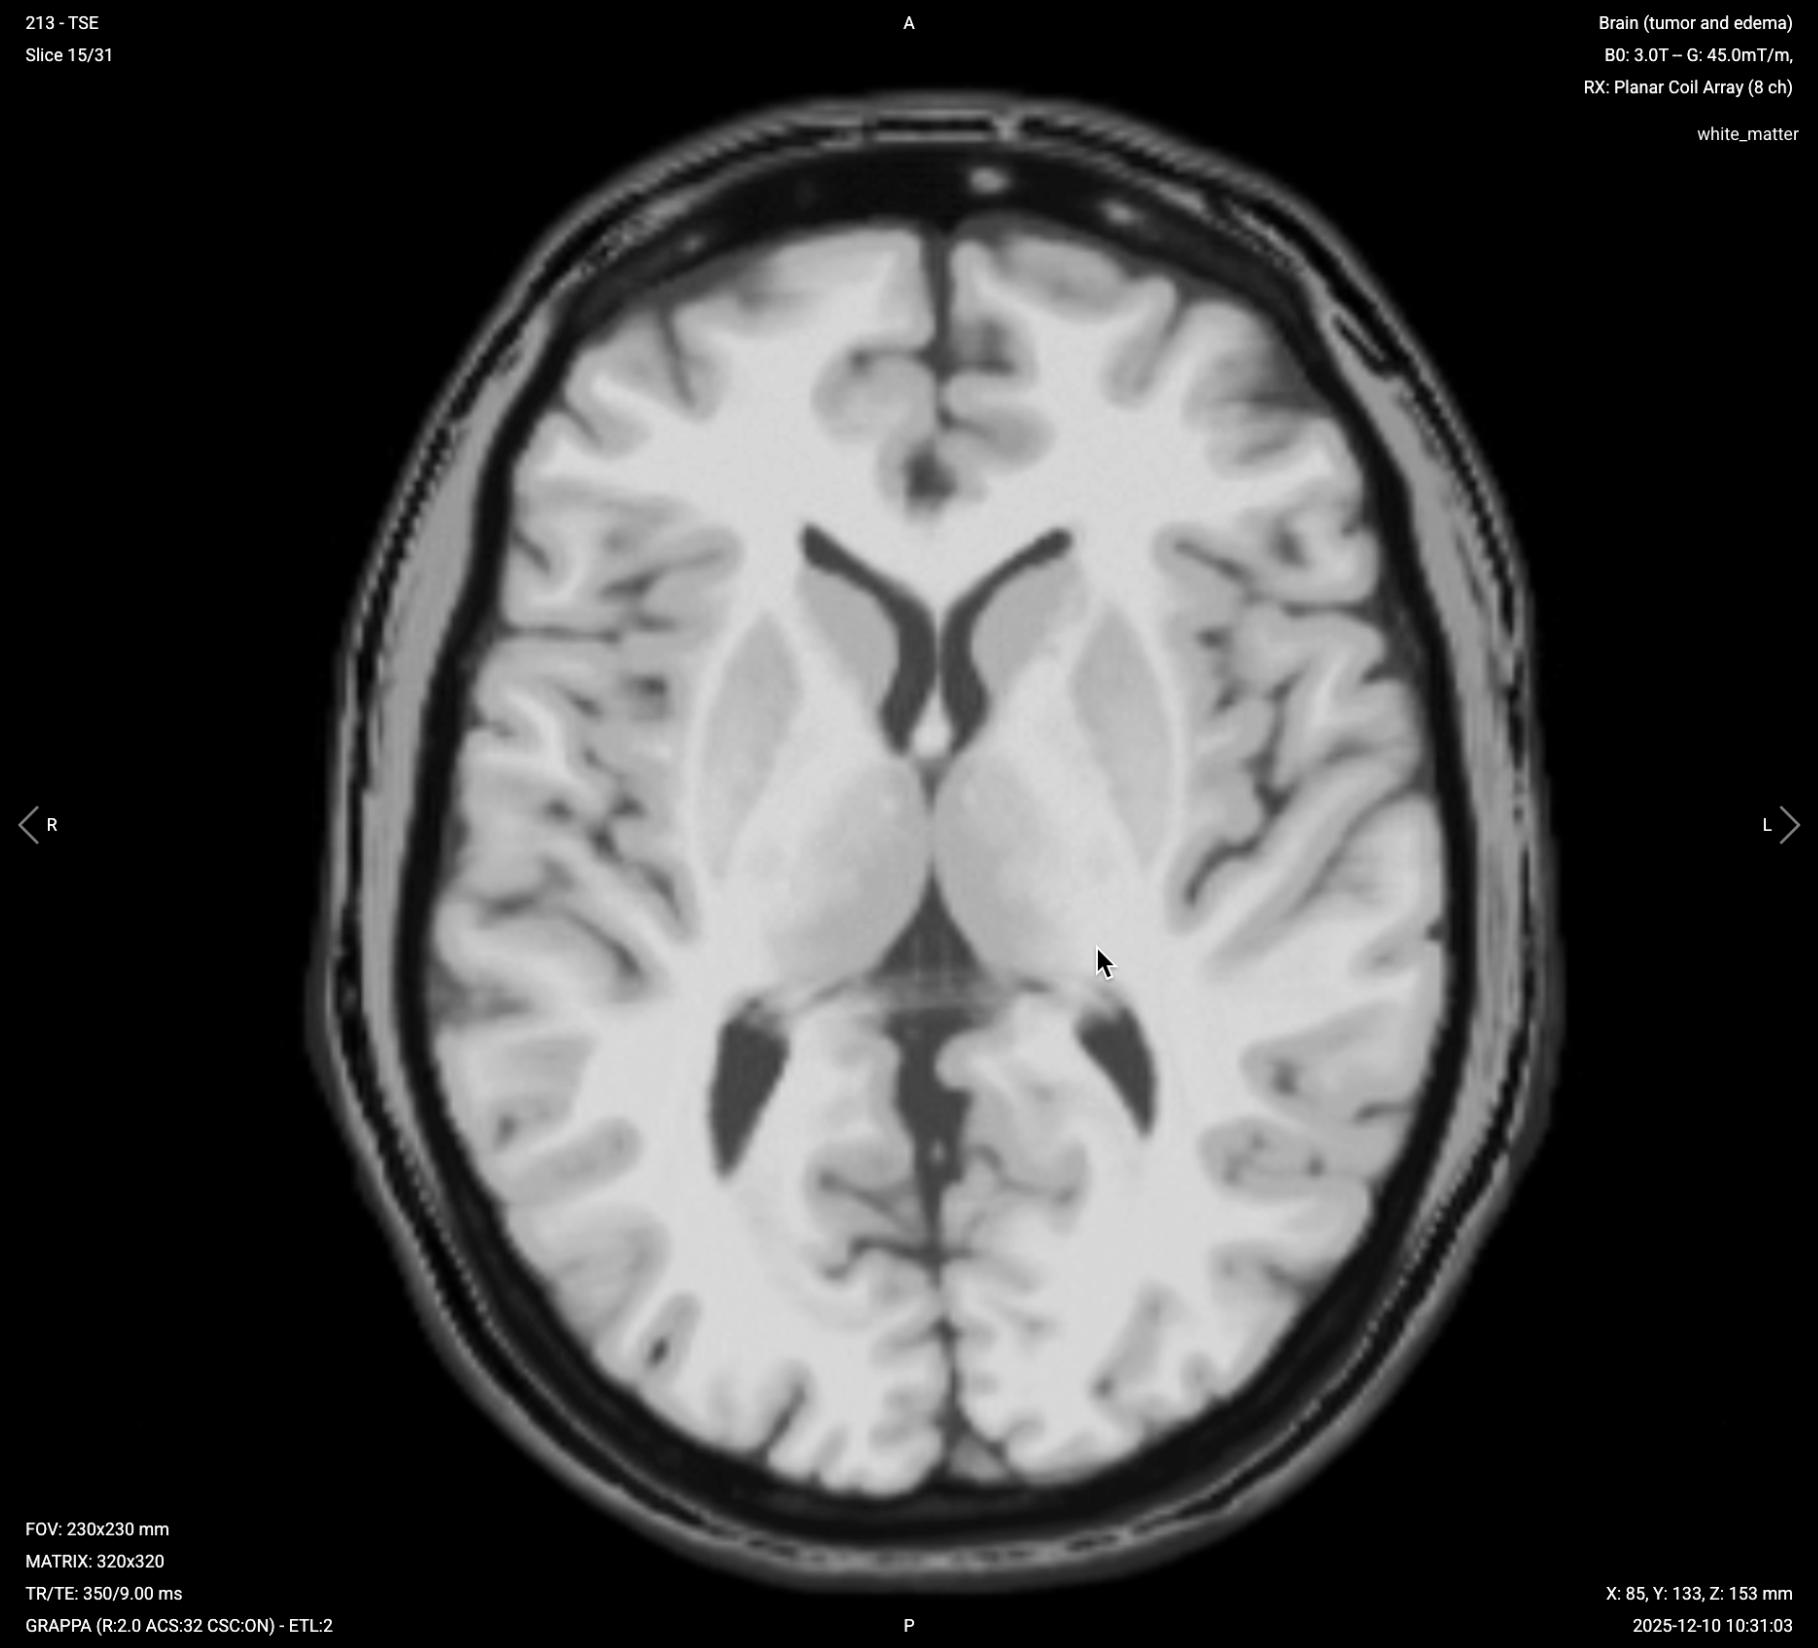

2. Planning Axial T1 TSE with Fat Suppression (Post-Contrast)

✅ Correct Planning:

Planning Axial T1 TSE with Fat Suppression (Post-Contrast) – Correct Planning

Planning Instructions:

• Copy the slice geometry and planning from the axial T2 TSE sequence.

• Keep the same slice angulation, coverage, and positioning to ensure images can be easily compared with other axial sequences.

• This sequence should be acquired at approximately 10-12 minutes post-injection for peak parenchymal enhancement.

Parameters for Post-Contrast Axial T1 TSE with Fat Suppression:

Parameter Recommended Values Why These Values

Echo Time (TE) 8–12 ms Short TE is required for T1 contrast.

Repetition Time (TR) 350–600 ms Short TR is required for T1 contrast.

Field-of-View (FOV) 210 × 250 mm Large enough to cover the brain while avoiding wrap-around artifacts.

Matrix 320 × 320 High matrix provides excellent spatial resolution for detecting small lesions.

Foldover Direction (Phase) Right-to-Left (RL) Reduces wrap-around artifacts and optimizes FOV for brain shape.

Number of Slices 30–35 Enough slices to fully cover from vertex to foramen magnum.

Slice Thickness 3–4 mm Thinner than routine brain (typically 5–6 mm) for better tumor detail.

Slice Gap 0–1 mm Minimal gap provides continuity between slices while avoiding cross-talk.

NEX / Averages 3 Higher averaging improves SNR for detecting subtle enhancement.

Turbo Factor / ETL 3–5 Low turbo factor maintains T1 weighting and avoids T2 contamination.

Bandwidth 244 Hz/px Medium bandwidth balances SNR with chemical shift artifacts.

Refocusing Flip Angle 180° Standard refocusing angle for TSE sequences.

Fold-over Suppression Yes Prevents wrap-around artifacts from posterior structures.

Fat Suppression Spectral Eliminates fat signal to make true contrast enhancement clearly visible.

Post-Contrast Axial T1 with Fat Suppression – Confirms Enhancement Patterns

Post-contrast T1 with fat suppression eliminates bright signal from fat, making true contrast enhancement stand out more clearly.

In brain tumor imaging, axial post-contrast T1 with fat suppression confirms enhancement patterns seen on the 3D MP-RAGE from a different angle. Fat suppression helps distinguish true enhancement from fat or hemorrhage, particularly near the skull base or in extraaxial tumors. This sequence provides peak parenchymal enhancement when acquired at 10-12 minutes post-injection, making subtle tumor enhancement more visible.

We acquire this sequence in axial orientation to match other standard axial sequences and enable direct comparison with pre-contrast images.

Axial T1 with Fat Suppression (Post-Contrast) – Correct Image Example:

Axial T1 with Fat Suppression (Post-Contrast) – Correct Image Example

Things to Look for in Post-Contrast Axial T1 with Fat Suppression:

• Confirmation of enhancement patterns from different angle

• Subtle enhancement that may be obscured by fat without suppression

• Clear distinction between enhancement and hemorrhage or fat

• Relationship of enhancing tumor to surrounding structures

• Absence of fat signal near skull base clarifying true enhancement